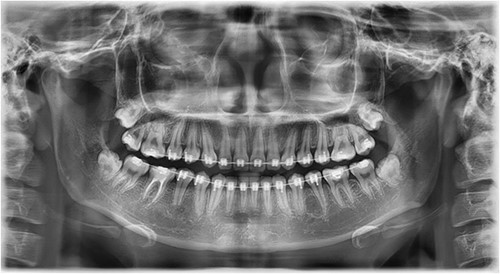

A Neumann full-thickness buccal flap was utilized to remove these during the course of orthodontic treatment. The shortcoming of the buccal surgical removal approach is that although it is better for visualization, it poses a high risk of trauma to the adjacent teeth or nerves [4, 5]. As the premolar was being removed on the right side, there was a fracture of the root apex (Fig. 2). On the left side, the premolar bud could be removed without any trauma to the adjacent tooth roots. After months of follow-up, there was normal bone formation, and no other symptoms were identified (Fig. 3).

Follow-up panoramic 1 week after removal of the supernumerary premolars.